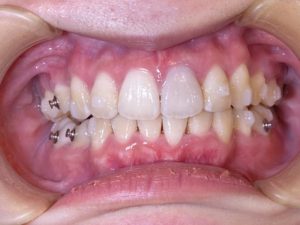

結婚式、前撮りまでに歯並びを治したい患者様👰

予定日まで1年、ここまで綺麗になりました✨

before→

after←

治療内容:マウスピース矯正中

抜歯治療(上下左右4本)

前歯のガタつきが主訴の患者様

抜歯も行いましたが、なんとか結婚式に間に合いました🙄

比べてみると、歯のアーチがとても綺麗になったのがよく分かりますね!